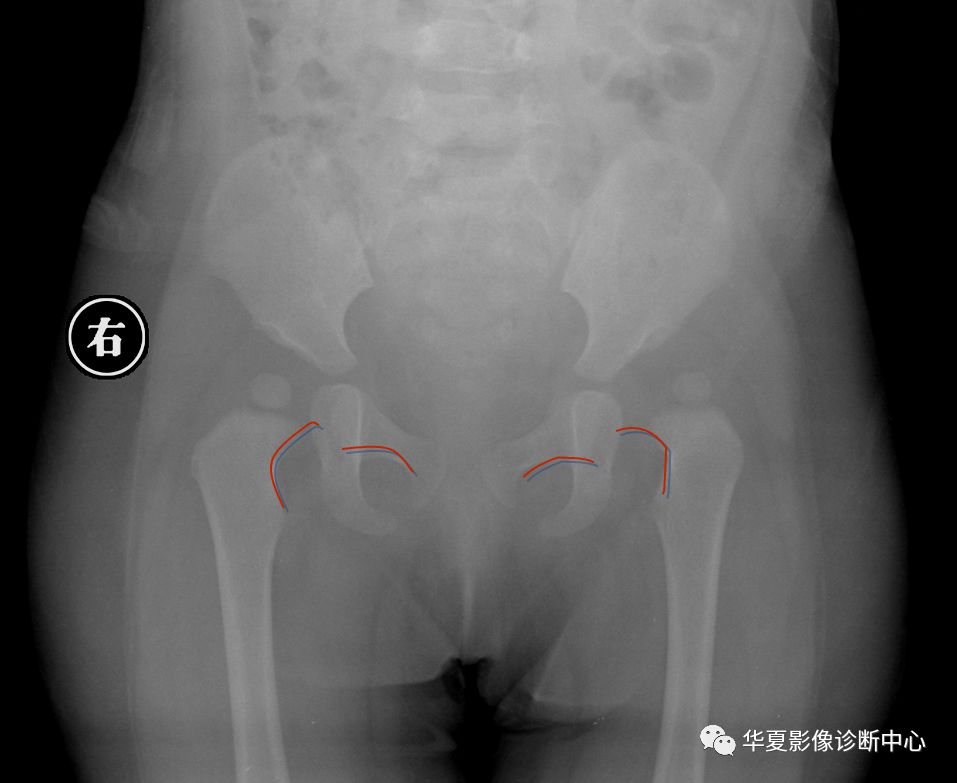

6. Shenton线:

正常闭孔上缘弧形线与股骨颈内侧弧形线相连在一个抛物线上,称为Shenton线,髋脱位、半脱位病例,此线完整性消失。

7.外侧线(Calve线)

外侧线(Calve线)即髂翼的外侧面与股骨颈外侧面的弧形连线,正常为连续的。